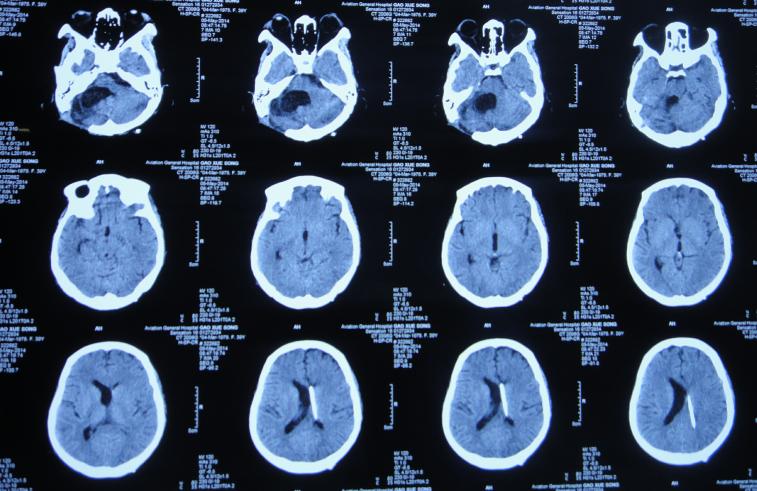

入院时头颅CT示右侧小脑半球低密度影,第四脑室扩张(图-14)。肺片肺部感染(片子丢失);重度贫血,血小板降低,白细胞减少。

图-14:2014年3月20日头颅CT